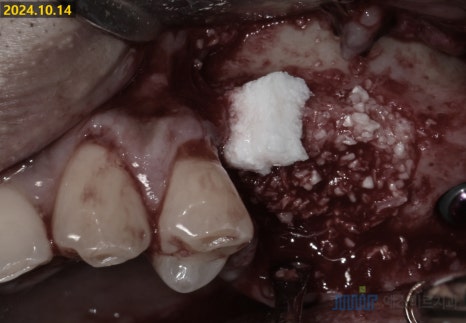

🔹 2. 상악동 거상술 + 뼈이식

상악동에 뼈가 거의 없는 상태였기 때문에

상악동 거상술(sinus lift)와 뼈이식, 골유도재생술을

함께 진행했습니다

아래 환자의 경우,

뼈상태가 좋지 않아서

상악동 거상술 (Sinus lift)을 통해 이식재가 들어갈 자리를 만들어주었고,

뼈이식 (Bone Grafting)을 통해 뼈를 가득 채워 넣었습니다

뼈이식재가 단단하게 자리 잡을 수 있도록

골유도 재생술 (Guided Bone Regeneration with membrane)을 함께 진행 후

임플란트 식립까지 당일에 완료했습니다

뼈이식과 골유도재생술을 동반한 임플란트식립